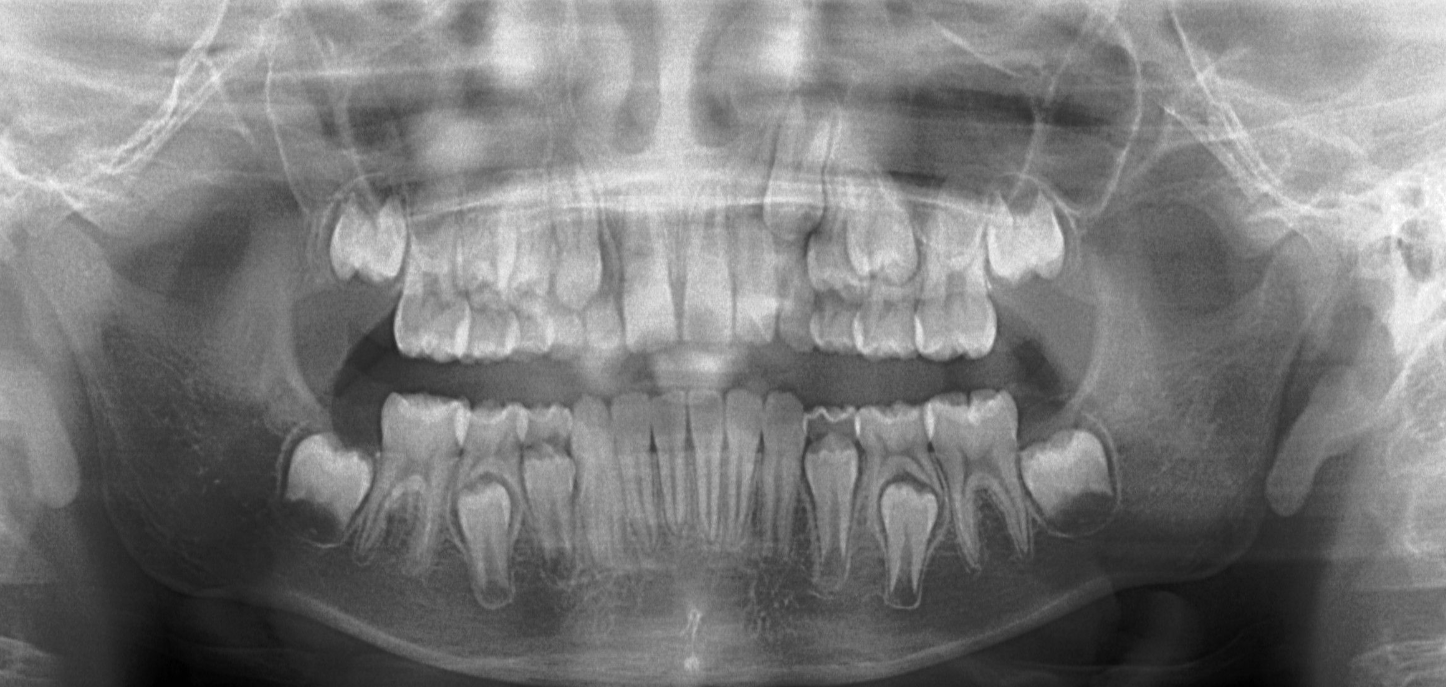

2.4 歯並びへの影響

口呼吸が原因で歯並びが悪くなる理由は、唇を閉じていないことにより、舌の位置が適切でなくなるためです。

舌が歯に押し付けることがなくなると、歯の位置がずれやすくなります。

これが長期間続くと、歯並びに悪影響を与え、将来的に矯正治療を必要とすることがあります。

これらの特徴が続くと、顔のバランスが崩れ、見た目にも影響を与えるだけでなく、歯並びにも悪影響を及ぼすことがあります。

特に、下顎が後ろに引っ込むことで、歯並びが悪くなるリスクが高まります。

これにより、将来的に矯正治療が必要になる可能性も出てきます。